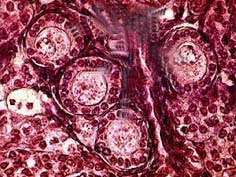

如图,可将卵泡的生长过程分为以下几个阶段 ( ) 1NS-02441.jpg 1NS-02442.jpg 1NS-02443.jpg 1NS-02444.jpg

• A.排卵前卵泡

• B.始基卵泡

• C.卵泡闭锁

• D.窦状卵泡

• E.窦前卵泡